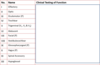

List the ‘12’ Cranial Nerves and their modalities

CN I olfactory nerves (special sensory)

CN II optic nerves (special sensory)

CN III oculomotor nerves (motor & parasympathetic)

CN IV trochlear nerves (motor)

CN V trigeminal nerves (CN V1 & V2: sensory only*; V3 is sensory & motor*)

CN VI abducent nerves (motor)

CN VII facial nerves (special sensory; motor & parasympathetic)

CN VIII vestibulocochlear nerves (special sensory)

CN IX glossopharyngeal nerves (special sensory; sensory; motor & parasympathetic)

CN X vagus nerves (sensory; motor; parasympathetic)

CN XI spinal accessory nerves (motor)

CN XII hypoglossal nerves (motor)